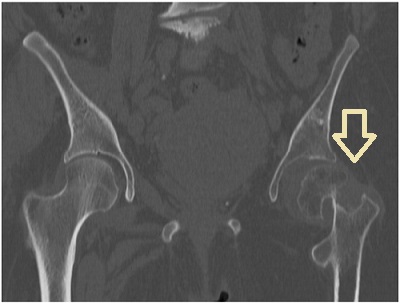

心房細動(Af)や狭心症から甲状腺機能亢進症/バセドウ病がみつかる場合もあります。[Nihon Ronen Igakkai Zasshi. 1996 Mar;33(3):191-5.] - 特に老年期女性は元々、閉経後骨粗鬆症があるため、さらに骨が悪くなる。[高齢者バセドウ病の大腿骨頚部骨折と大腿骨転子部骨折(脚の付け根の骨折)]

加齢による骨粗しょう症で、ただでさへ骨折しやすいのに、高齢の甲状腺機能亢進症/バセドウ病患者は、甲状腺ホルモンの作用で骨分解が加速され、輪をかけて骨折の危険が高くなります(甲状腺機能亢進症/バセドウ病の骨粗しょう症 )。

高齢者の大腿骨頚部骨折後に骨接合術をしなければ寝たきりになり、認知症・筋肉量減少によるサルコペニアが進行します。転倒しやすい生活環境を改善し、ヒッププロテクターを装着するのもよいでしょう。